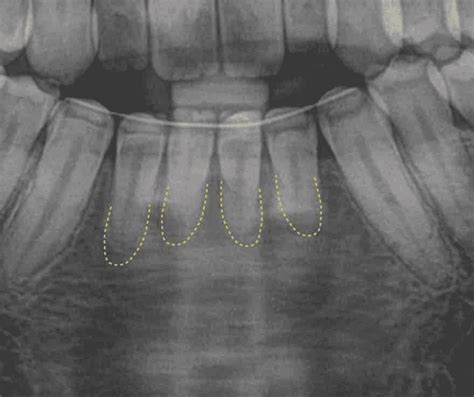

La reabsorción radicular es la pérdida de tejido dental como resultado de la acción odontoclástica. De forma general, la podemos clasificar en interna y externa; sin embargo, existen muchos tipos y sub divisiones. La reabsorción radicular apical externa (RRAE) se describe como un proceso fisiológico o patológico con pérdida de cemento o dentina, dando como resultado un acortamiento del ápice de la raíz.

La pérdida de raíz es conocida como «reabsorción radicular externa«, y es una de las secuelas más habituales del tratamiento de ortodoncia. Aunque suele ser leve y casi imperceptible en la mayoría de los casos, es un proceso natural de remodelación del hueso alrededor del diente, aunque a veces puede ocurrir un exceso de reabsorción debido a diversas razones como la fuerza aplicada por el aparato, el tiempo de tratamiento, la forma de la raíz y la predisposición personal de los dientes.